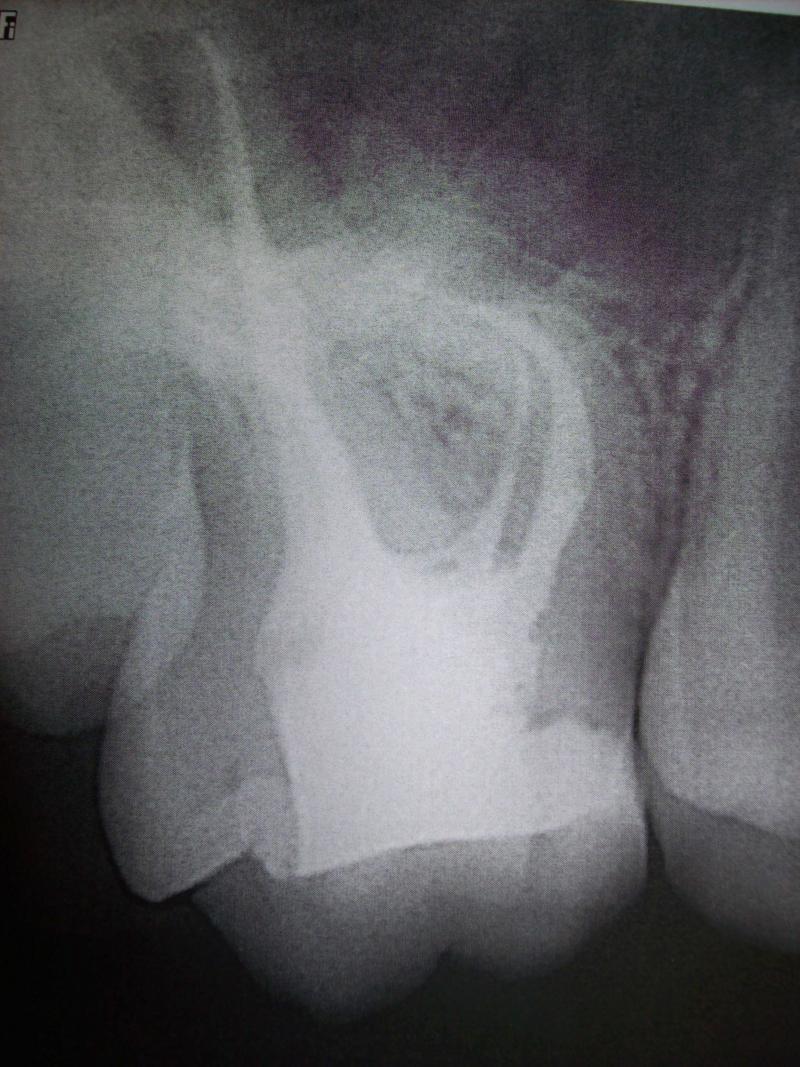

DR JET LOVES ROOT CANALS

ATTENTION!!! We DO NOT accept insurances . DR. JET ONLY DOES FIRST TIME ROOT CANALS THAT HAVE NOT ALREADY BEEN DONE. HE DOES NOT DO RETREATMENTS, TEETH THAT HAVE CROWNS OR BRIDGES, OR WISDOM TEETH. WE HAVE BEEN SERVING THE COMMUNITY FOR MANY YEARS . WE LOVE TO HELP PEOPLE AND WE APPRECIATE YOUR BUSINESS. THANK YOU!!!

General Dentist, Performs Root Canals ONLY - Microscope Trained Dentist

"DR. JET'S MISSION IS TO PERFORM ROOT CANALS FOR A REDUCED FEE USING THE LATEST TECHNOLOGY AND TECHNIQUES TO SERVICE THE MANY PEOPLE WHO ARE UNINSURED OR UNDER-INSURED GIVING EVERYONE AN OPPORTUNITY TO SAVE THEIR TOOTH!"

**PLEASE BE AWARE THAT A ROOT CANAL IS AN ATTEMPT TO SAVE YOUR ALREADY DAMAGED TOOTH. THERE IS NO GUARANTEE THAT ANY TOOTH CAN BE SAVED BUT DR JET WILL DO HIS BEST TO HELP YOU. THE OTHER OPTION IS TO EXTRACT YOUR TOOTH